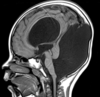

Q

A

Esclerose mesial temporal

Observe a perda de volume, que indica atrofia e causa aumento secundário do corno temporal do ventrículo lateral.

O sinal alto no hipocampo reflete a gliose.